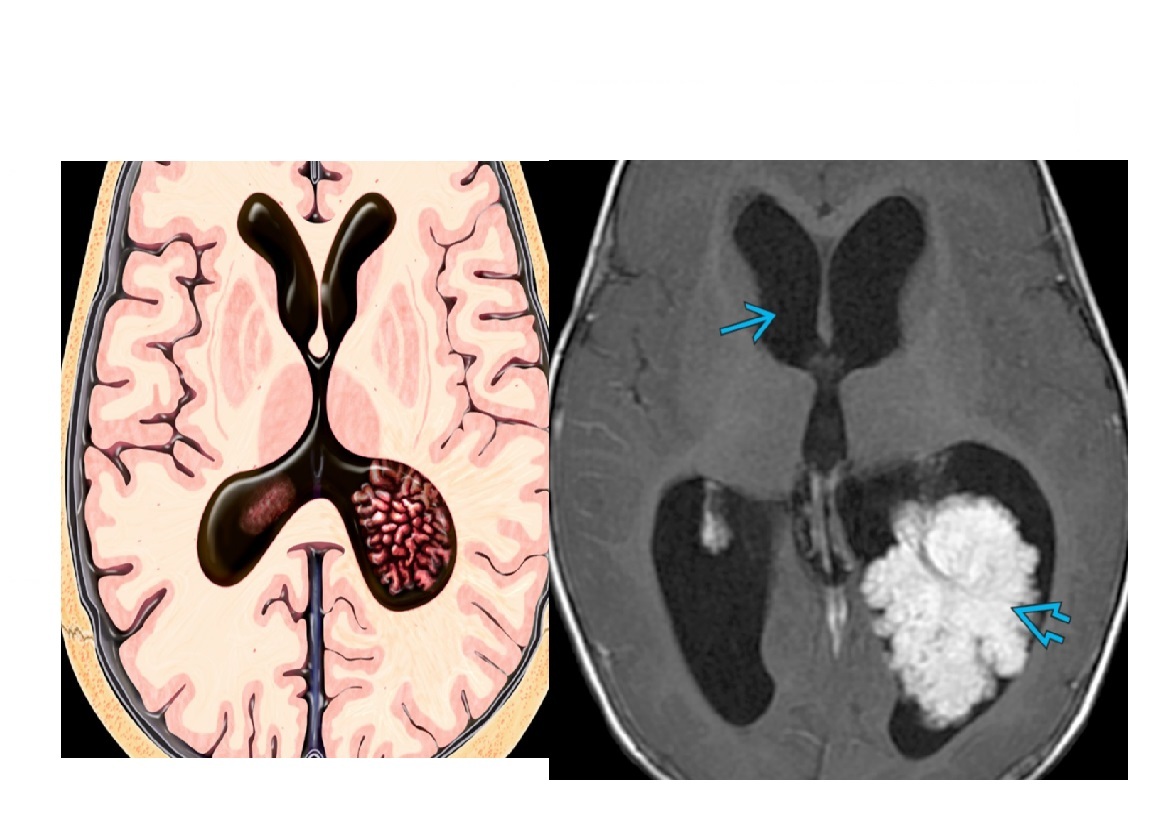

Intraventricular lobulated mass in trigone of lateral ventricle. Smooth, large and small foci of calcification on CT. Lateral ventricle is dilated?

A

Choroid plexus papilloma

Hyperdense on CT.

Iso on T1 and hyperintense on T2.

**Intense homogenous enhancement. **

Nb in adults - occur predominantly in 4th ventricle